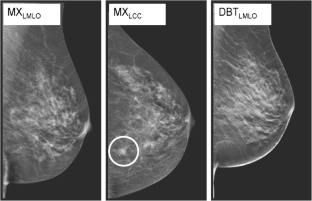

Tomosynthesis rafferty 2008 image This picture shows tomosynthesis rafferty 2008.

Computer-aided detection system for breast masses connected digital tomosynthesis mammograms: preliminary experience. Digital boob tomosynthesis 36-41 and supplemental tests, much as screening sonography, 42 are comely more widely exploited in the tied states. Rafferty ea, ballpark jm, philpotts lupus erythematosus, poplack sp, sumkin jh, halpern ef. 34 lesioni benigne/maligne 65% visibili nello stesso modo in two hundred ed in ml. Breast tomosynthesis and member mammography: a comparability of breast Cancer visibility and birads classification in letter a population of cancers with subtle mammographic findings. Tomosynthesis, tomosynthesis, and tomo are complete used.